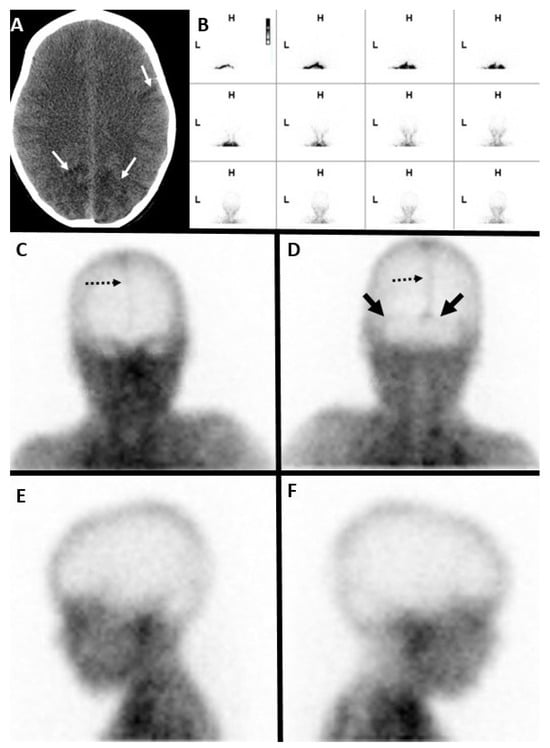

7.1. Nuclear Scintigraphy

- Donohoe, K.J.; Frey, K.A.; Gerbaudo, V.H.; Mariani, G.; Nagel, J.S.; Shulkin, B. Procedure guideline for brain death scintigraphy. J. Nucl. Med. 2003, 44, 846–851. [Google Scholar] [PubMed]

- Donohoe, K.J.; Agrawal, G.; Frey, K.A.; Gerbaudo, V.H.; Mariani, G.; Nagel, J.S.; Shulkin, B.L.; Stabin, M.G.; Stokes, M.K. SNM practice guideline for brain death scintigraphy 2.0. J. Nucl. Med. Technol. 2012, 40, 198–203. [Google Scholar] [CrossRef] [PubMed]

- Al-Shammri, S.; Al-Feeli, M. Confirmation of brain death using brain radionuclide perfusion imaging technique. Med. Princ. Pract. 2004, 13, 267–272. [Google Scholar] [CrossRef] [PubMed]

- Rizvi, T.; Batchala, P.; Mukherjee, S. Brain Death: Diagnosis and Imaging Techniques. Semin. Ultrasound CT MR 2018, 39, 515–529. [Google Scholar] [CrossRef] [PubMed]

- de la Riva, A.; González, F.M.; Llamas-Elvira, J.M.; Latre, J.M.; Jiménez-Heffernan, A.; Vidal, E.; Martínez, M.; Torres, M.; Guerrero, R.; Alvarez, F.; et al. Diagnosis of brain death: Superiority of perfusion studies with 99Tcm-HMPAO over conventional radionuclide cerebral angiography. Br. J. Radiol. 1992, 65, 289–294. [Google Scholar] [CrossRef] [PubMed]

- Wilson, K.; Gordon, L.; Selby, J.B., Sr. The diagnosis of brain death with Tc-99m HMPAO. Clin. Nucl. Med. 1993, 18, 428–434. [Google Scholar] [CrossRef] [PubMed]

- Zuckier, L.S.; Kolano, J. Radionuclide studies in the determination of brain death: Criteria, concepts, and controversies. Semin. Nucl. Med. 2008, 38, 262–273. [Google Scholar] [CrossRef] [PubMed]

- Bertagna, F.; Barozzi, O.; Puta, E.; Lucchini, S.; Paghera, B.; Savelli, G.; Panarotto, B.; Rodella, C.A.; Rebuffoni, L.; Bosio, G.; et al. Residual brain viability, evaluated by (99m)Tc-ECD SPECT, in patients with suspected brain death and with confounding clinical factors. Nucl. Med. Commun. 2009, 30, 815–821. [Google Scholar] [CrossRef] [PubMed]

- Munari, M.; Zucchetta, P.; Carollo, C.; Gallo, F.; De Nardin, M.; Marzola, M.C.; Ferretti, S.; Facco, E. Confirmatory tests in the diagnosis of brain death: Comparison between SPECT and contrast angiography. Crit. Care Med. 2005, 33, 2068–2073. [Google Scholar] [CrossRef] [PubMed]

- Bonetti, M.G.; Ciritella, P.; Valle, G.; Perrone, E. 99mTc HM-PAO brain perfusion SPECT in brain death. Neuroradiology 1995, 37, 365–369. [Google Scholar] [CrossRef] [PubMed]

- Appelt, E.A.; Song, W.S.; Phillips, W.T.; Metter, D.F.; Salman, U.A.; Blumhardt, R. The “hot nose” sign on brain death nuclear scintigraphy: Where does the flow really go? Clin. Nucl. Med. 2008, 33, 55–57. [Google Scholar] [CrossRef] [PubMed]

- Mrhac, L.; Zakko, S.; Parikh, Y. Brain death: The evaluation of semi-quantitative parameters and other signs in HMPAO scintigraphy. Nucl. Med. Commun. 1995, 16, 1016–1020. [Google Scholar] [CrossRef] [PubMed]

- Lee, V.W.; Hauck, R.M.; Morrison, M.C.; Peng, T.T.; Fischer, E.; Carter, A. Scintigraphic evaluation of brain death: Significance of sagittal sinus visualization. J. Nucl. Med. 1987, 28, 1279–1283. [Google Scholar] [PubMed]